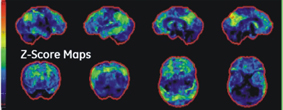

此外,我們也利用新的3D立體定向表面投影技術,及與資料庫中正常模組比較差異等技術,來增加檢查的準確性。

全面自動化立體影像校正

全腦部立體投影技術

▲自動與正常資料庫比對,標定代謝低下區域